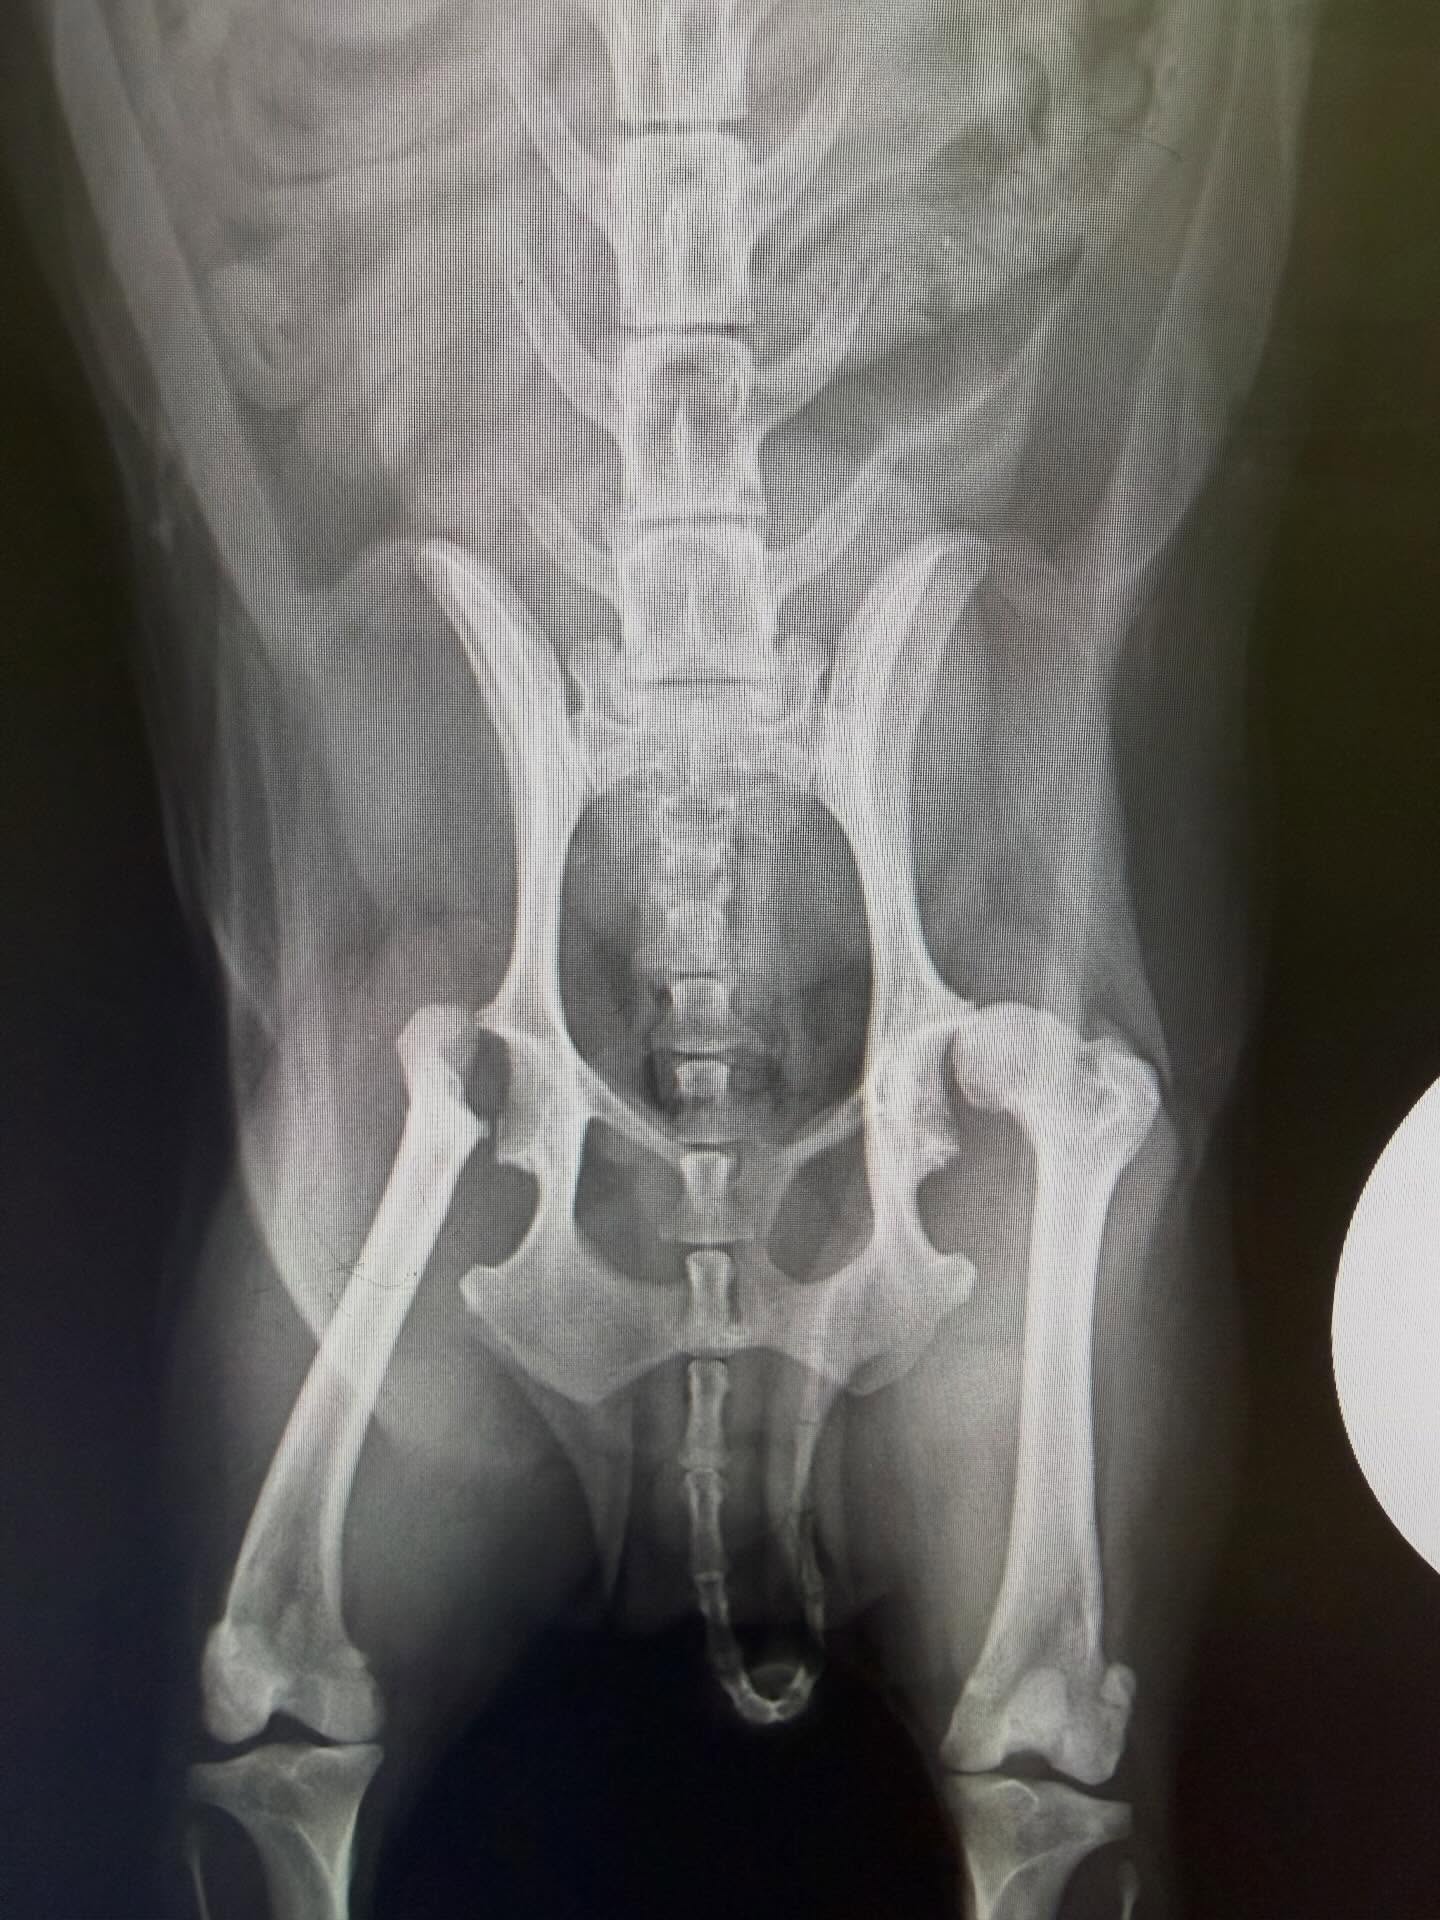

“股関節の手術”

過去に片方の股関節を手術したワンちゃん。反対側の股関節も関節炎が進行し、変形してきて、しかも亜脱臼の兆候も出てきていたため、反対側の手術を行いました。

人間でも股関節の病気は多く、中高齢になると発症することが多い病気。人間では人工股関節の手術も進化し、動物でも人工股関節の手術は高度獣医療施設で可能ですが、費用も高額。ですので、大腿骨頭骨頚部切除術という太ももの骨の頭を切る手術が一般的です(画像参照)。特に、消炎鎮痛剤による内科的な維持をすることもありますが、薬を飲んでも痛みが出てきたり、長期使用による腎臓負担のリスクや、体重が重い子ほど将来的に進行する可能性が高く、予防的に手術する場合があります。